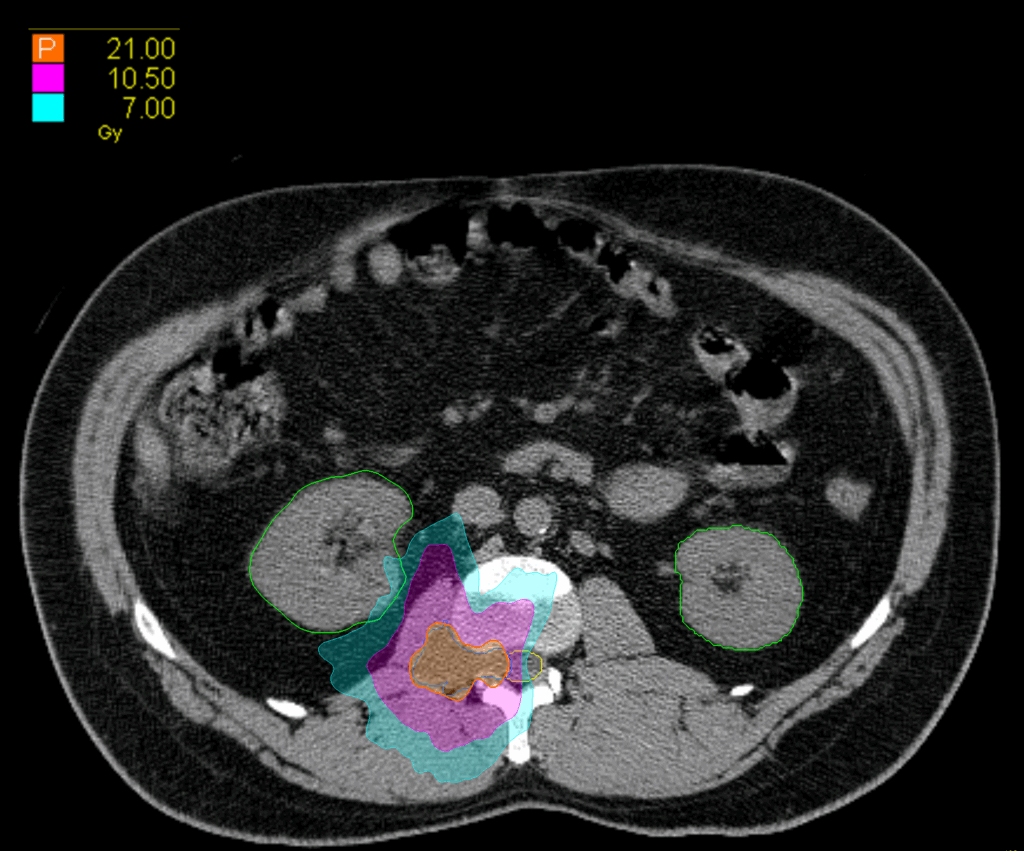

Treatment Plan Images

Fractionation

21 Gy in 3 fractions

PTV(s) Volume

PTV, 15.7 cc

Dose Distributions

- Prescription to the 77.9% isodose line

- Max. dose 29 Gy